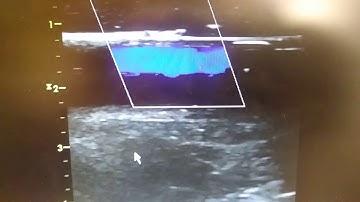

Open-source Fully-Programmable Flow Phantom for Doppler Ultrasound